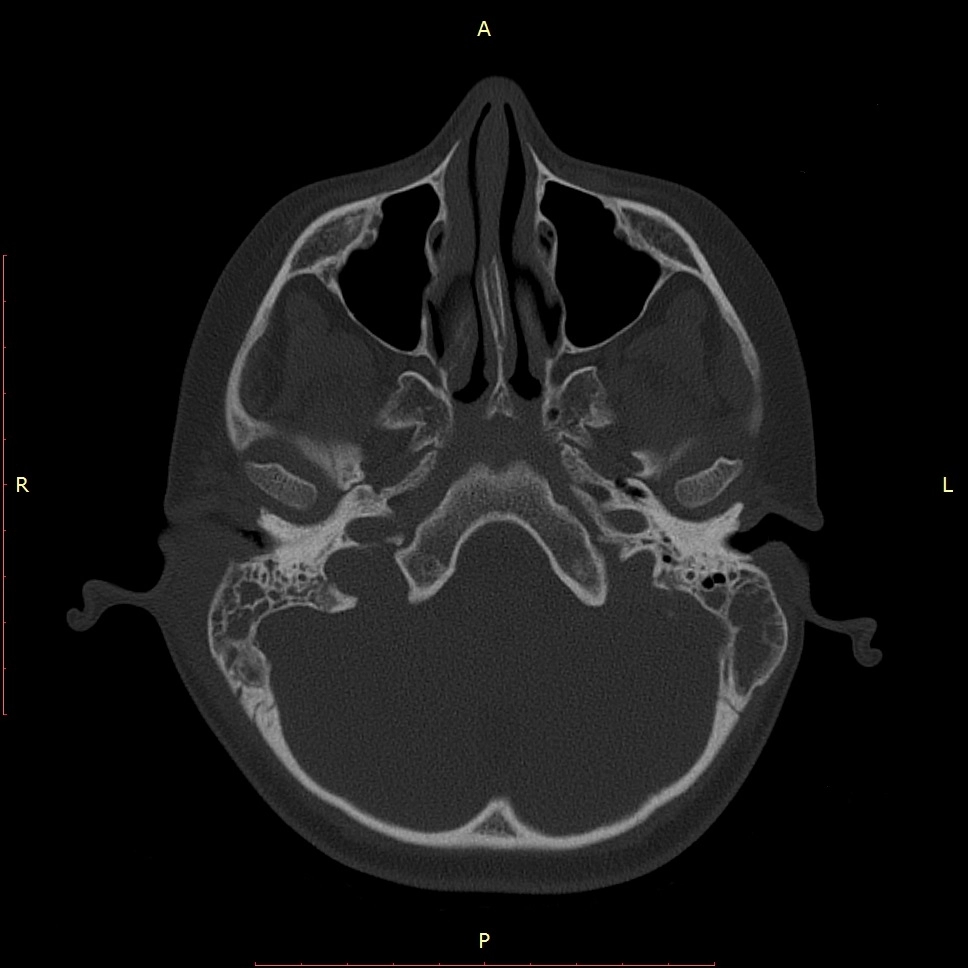

КТ височных костей

КТ височных костейПри заболеваниях, связанных с нарушениями органов слуха или вестибулярного аппарата, а также при повреждениях черепа часто возникает необходимость в КТ височных костей. Это исследование позволяет построить трехмерную компьютерную модель этой области черепа пациента и выявить нарушения структуры костной и хрящевой ткани, а также другие патологии. Оно выполняется при помощи просвечивания черепа слабым рентгеновским излучением с регистрацией прохождения луча специальными чувствительными датчиками. Сканирование выполняется послойно, получаемая информация обрабатывается компьютером, а результат выводится на экран томографа и фиксируется в его памяти.

Что показывает КТ височных костей?

Компьютерная томография височных костей позволяет обнаружить широкий спектр заболеваний и травматических патологий:

• опухоли и другие новообразования в костной ткани и слуховом аппарате;

• воспалительные очаги;

• дегенеративные изменения тканей;

• кровоизлияния, отеки, ущемления нервных волокон;

• переломы и трещины костей.

Результаты исследования представляются в виде трехмерной модели височных костей пациента со всеми характерными изменениями и аномалиями развития.